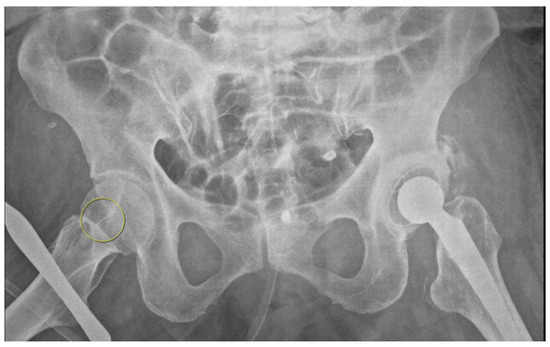

An 87-year-old female patient came to the emergency department with increased bilateral pleural effusion with pneumonia, and she was admitted for treatment. She had been bedridden with comorbidities, including old cerebral infarction, hypertension, and had left femur neck fracture with endoprosthesis for 4 weeks before admission. Her body mass index was 26.67 kg/m2. She was generally edematous. We drained pleural effusion, diagnosed as parapneumonic effusion, and administered intravenous antibiotics for the treatment of pneumonia with parapneumonic effusion. During hospitalization, her conditions were wax and wane, with aspiration pneumonia. On day 37 of hospitalization, her blood pressure was consistently low despite the use of a vasopressor. For arterial blood gas analysis (ABGA) to monitor the patient’s state of acidosis, we repeatedly performed puncture of the right femoral artery instead of the radial or dorsal artery. We used a 25 gauge and 16 mm length needle for femoral arterial puncture. After blood extraction, while drawing the syringe out of a femoral artery, the needle was disconnected from the syringe. The needle remained in the groin of the patient, and its location was not identified through portable ultrasonography. Radiography of the pelvic bone showed the needle fragment in the right groin (Figure 1). Fluoroscopic radiography revealed the exact location of the needle fragment (Figure 2). A surgical incision was performed to obtain the embedded needle in the soft tissue of the groin, without penetrating the femoral artery. The needle fragment was removed (Figure 3) completely without complications. The needle was bent as it was pulled out with mosquito forceps (Figure 3).

Figure 1. Radiography of pelvic bone. A needle fragment showed in the right groin (yellow circle).